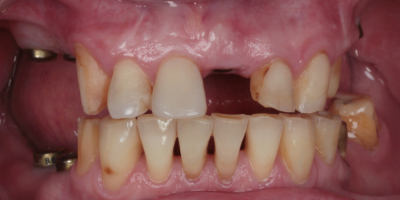

Пациентка обратилась с частичной потерей зубов на верхней и нижней челюсти. Отсутствие жевательных зубов и дефект в переднем отделе верхней челюсти мешали полноценно питаться и отражались на эстетике улыбки.

Была проведена имплантация: установлены импланты в области жевательных зубов нижней челюсти и в зоне переднего зуба верхней челюсти. После остеонтеграции имплантатов - проведено протезирование циркониевыми коронками.